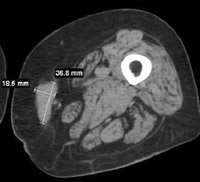

【投与前】

【投与後】

悪性黒色腫(メラノーマ)にテロメライシンを投与した例です。

これまたかなり分かりにくいんですが、若干、腫瘍が縮小しているのが分かるかと思います。

臨床評価が可能だった、9人中6人で腫瘍が6.6~35パーセント縮小したとのことです。